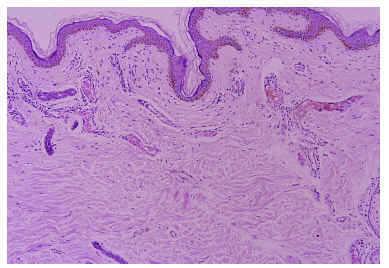

Se realizó una biopsia de la lesión, cuyo estudio histopatológico mostró una piel delgada, con atrofia epidérmica y con vasos dilatados en la dermis papilar y reticular revestidos por un endotelio de una capa celular sin atipias (fig. 2).

Fig. 2.--Vasos dilatados en la dermis papilar y reticular (HE, x100).